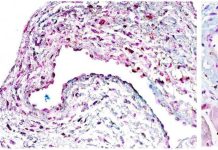

Células madre pueden ofrecer una nueva esperanza para el tratamiento de la enfermedad renal...

Más de 4 millones de personas en todo el mundo padecen enfermedad renal terminal que requiere hemodiálisis, un tratamiento en el que una máquina...